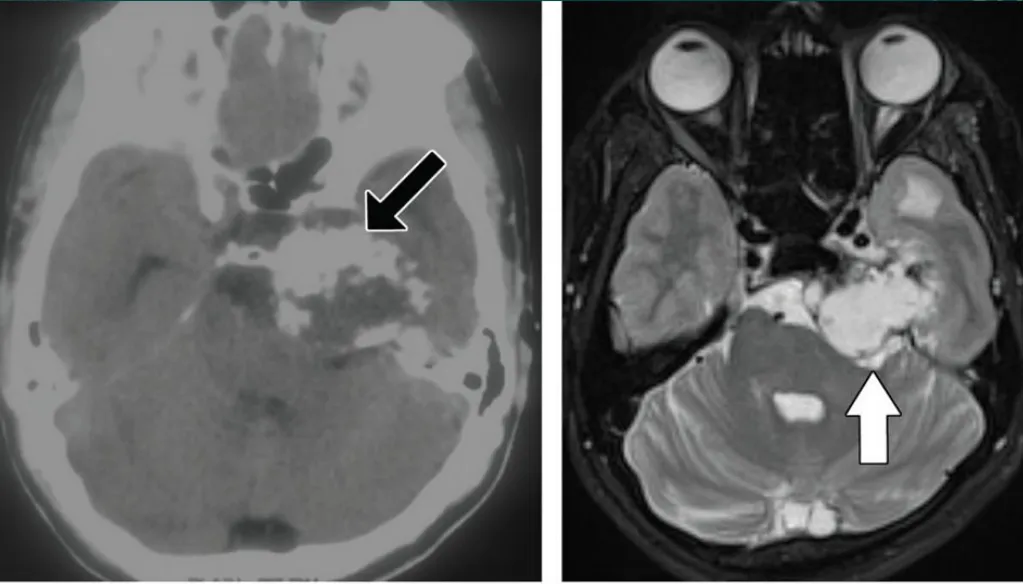

圖:海綿竇腦膜瘤合并左側(cè)頸內(nèi)動脈狹窄,手術(shù)難度大

海綿狀神經(jīng)鞘瘤,瘤內(nèi)間囊變,實性部分明顯強化。

圖:海綿狀神經(jīng)鞘瘤,瘤內(nèi)間囊變,實性部分明顯強化。

海綿竇血管瘤,T2高信號,累及左側(cè)Meckel腔

圖:海綿竇血管瘤,T2高信號,累及左側(cè)Meckel腔

軟骨肉瘤,巖尖膨脹性骨質(zhì)破壞,累及左側(cè)海綿竇后部

圖:軟骨肉瘤,巖尖膨脹性骨質(zhì)破壞,累及左側(cè)海綿竇后部

圖:海綿竇黑色素瘤,和海綿狀血管瘤容易混淆

圖:海綿竇區(qū)頸內(nèi)動脈瘤

海綿竇區(qū)表皮樣囊腫

圖:海綿竇區(qū)表皮樣囊腫